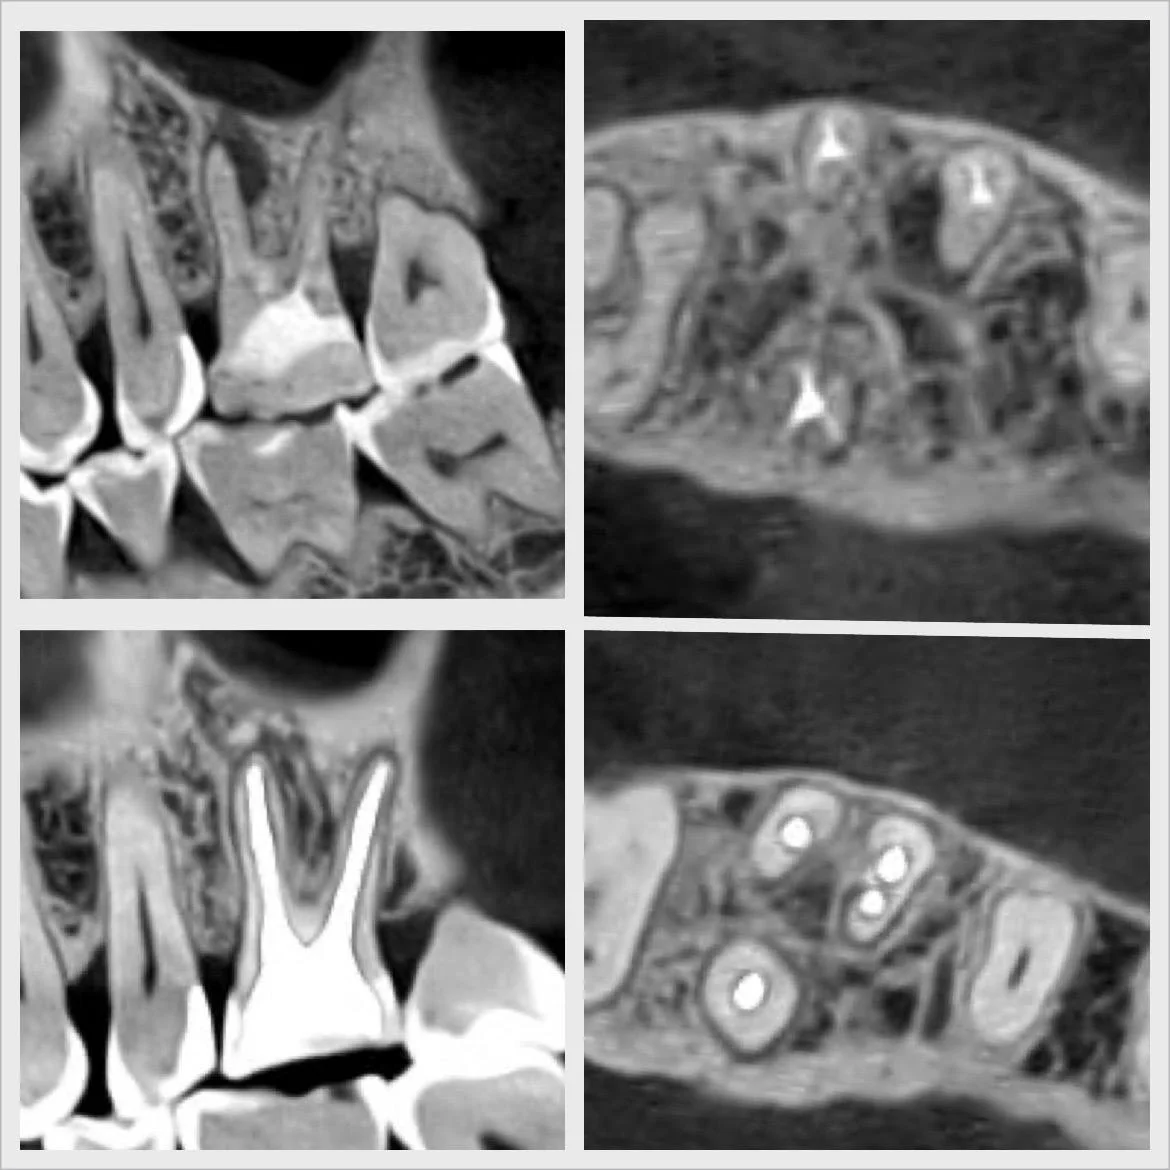

Efekty leczenia